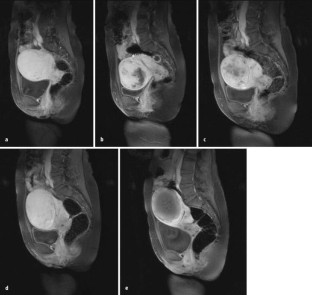

Abb. 3a–e